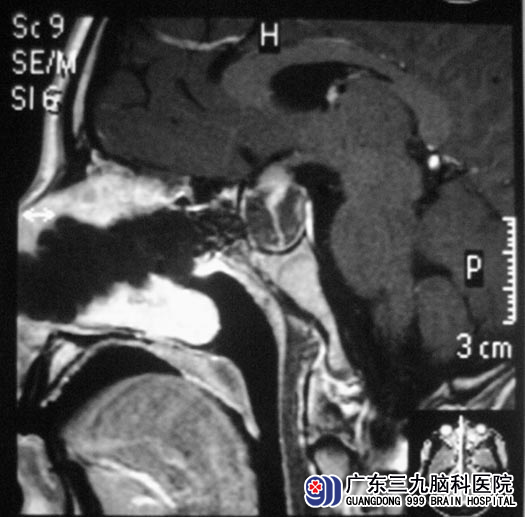

广东三九脑科医院垂体瘤诊疗中心 鲁明主任初步检查:视力、视野正常,查阅头颅MR见肿瘤向下生长,决定经鼻入路微创手术治疗。由鲁明主任主刀,在神经导航仪定位下行经鼻蝶垂体瘤切除术,术中见肿瘤呈灰白色,质软,易剔除,镜下行肿瘤切除术。术后小刘未出现脑脊液鼻漏等常见术后并发症,泌乳素水平基本恢复正常。术后病理结果为:垂体腺瘤。

▲手术后